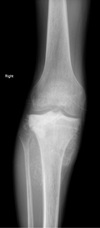

2

3

4

Perfectly